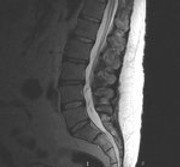

Was in der MRT Aufnahme Juli 2018 auffällig ist, sind die unterschiedlichen Höhen und die Farben der BS.

Je dunkler die BS, desto größer ist der festgestellte Wasserverlust der BS.

Diese Einbuchtungen an den Deckenplatten und hellen Stellen, sind aus meiner Sicht eher ein Hinweis auf Morbus Scheuerman.

Das ist eine Wachstumsstörung durch zu schnelles körperliches Wachstum in Kindheit und Jugend.

Die BWS zeigt auch schon schmale BS Fächer.

Was mir auch aufgefallen ist, dass die Aufnahme einen kl. Versatz von L5 zu S1 zeigt.

Zumindest steht L5 nicht mehr parallel zu S1 und kippt nach dorsal leicht ab

Das deutet auf Instabilität, bzw. Gleitwirbel hin und würde auch erklären, warum Stehen Beschwerden erzeugt.

Wurde schonmal gemacht. Die Bilder habe ich angefügt, ebenso ein upright MRT.

Bilder Funktionsröntgen: